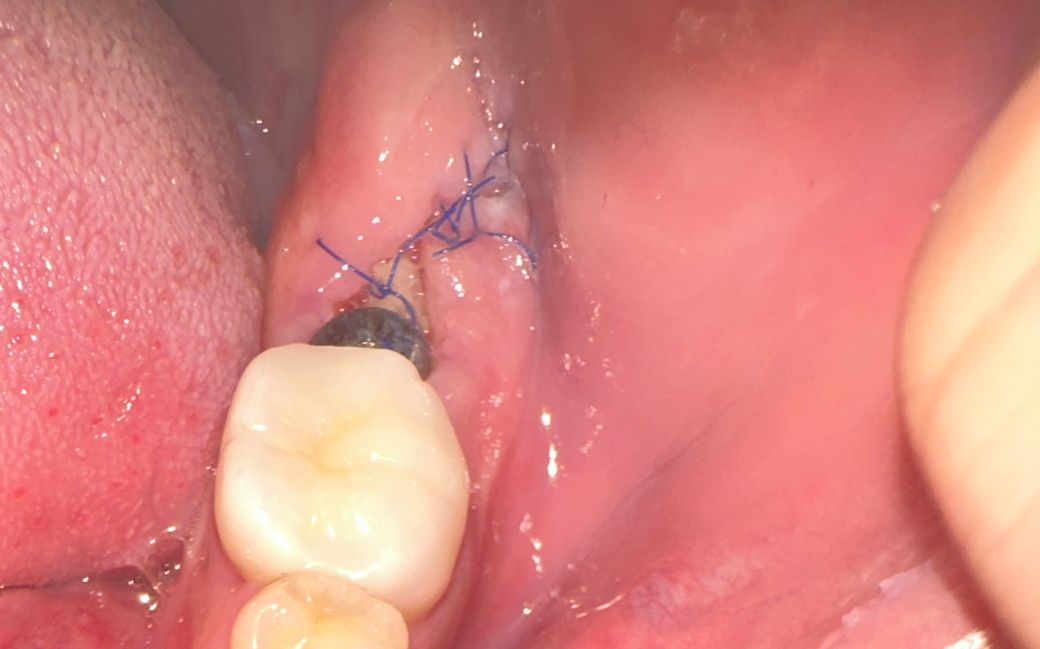

임플란트 식립후 잇몸 벌어짐 괜찮나요?

임플란트 식립후 1주일정도 되었고, 뒤쪽 잇몸 틈이 벌어진것같은데요 관리를 잘하고있다고 생각하는데 상태가 괜찮은건지요? 혹시나 재수술을해야하는건 아닌가싶어 다음주에 치과가기전에 미리 물어봅니다..

• 1번 째 사진

사진으로 봤을 때는 염증이 있는것으로 보이지는 않습니다.

현재 사진상으로는 큰 문제는 있어보이지는 않습니다. 잇몸이 아물면서 틈은 메꾸어지기에 걱정하지 않으셔도 됩니다.

크게 문제가 잇어 보이지 않습니다. 실밥이 잘 잇으니 너무 걱정하지 않으셔도 될것같습니다.

사진상으로는 잇몸은 적절한 치유 상태를 거치고 있는 것으로 보이며 점차 닫힙니다. 잇몸초기치유는 원래 1~2주 정도 걸립니다. 관리는 계속 잘해주셔야 합니다. 수술 후 1주일이 지났으므로 평상시처럼 그쪽부위로도 식사 하시고 양치질을 잘 해주셔야 합니다. 다만, 임플란트 뚜껑 튀어나온 부위(힐링 어버트먼트)에 자꾸 혀를 가져다대거나 그러는 것은 뚜껑이 풀려 탈락할 수 있으므로 지양해야 합니다. 10~14일 정도 후에 실밥을 풀러갈텐데 치과에서도 잇몸 치유 상태가 괜찮은지 봐줄 것입니다.